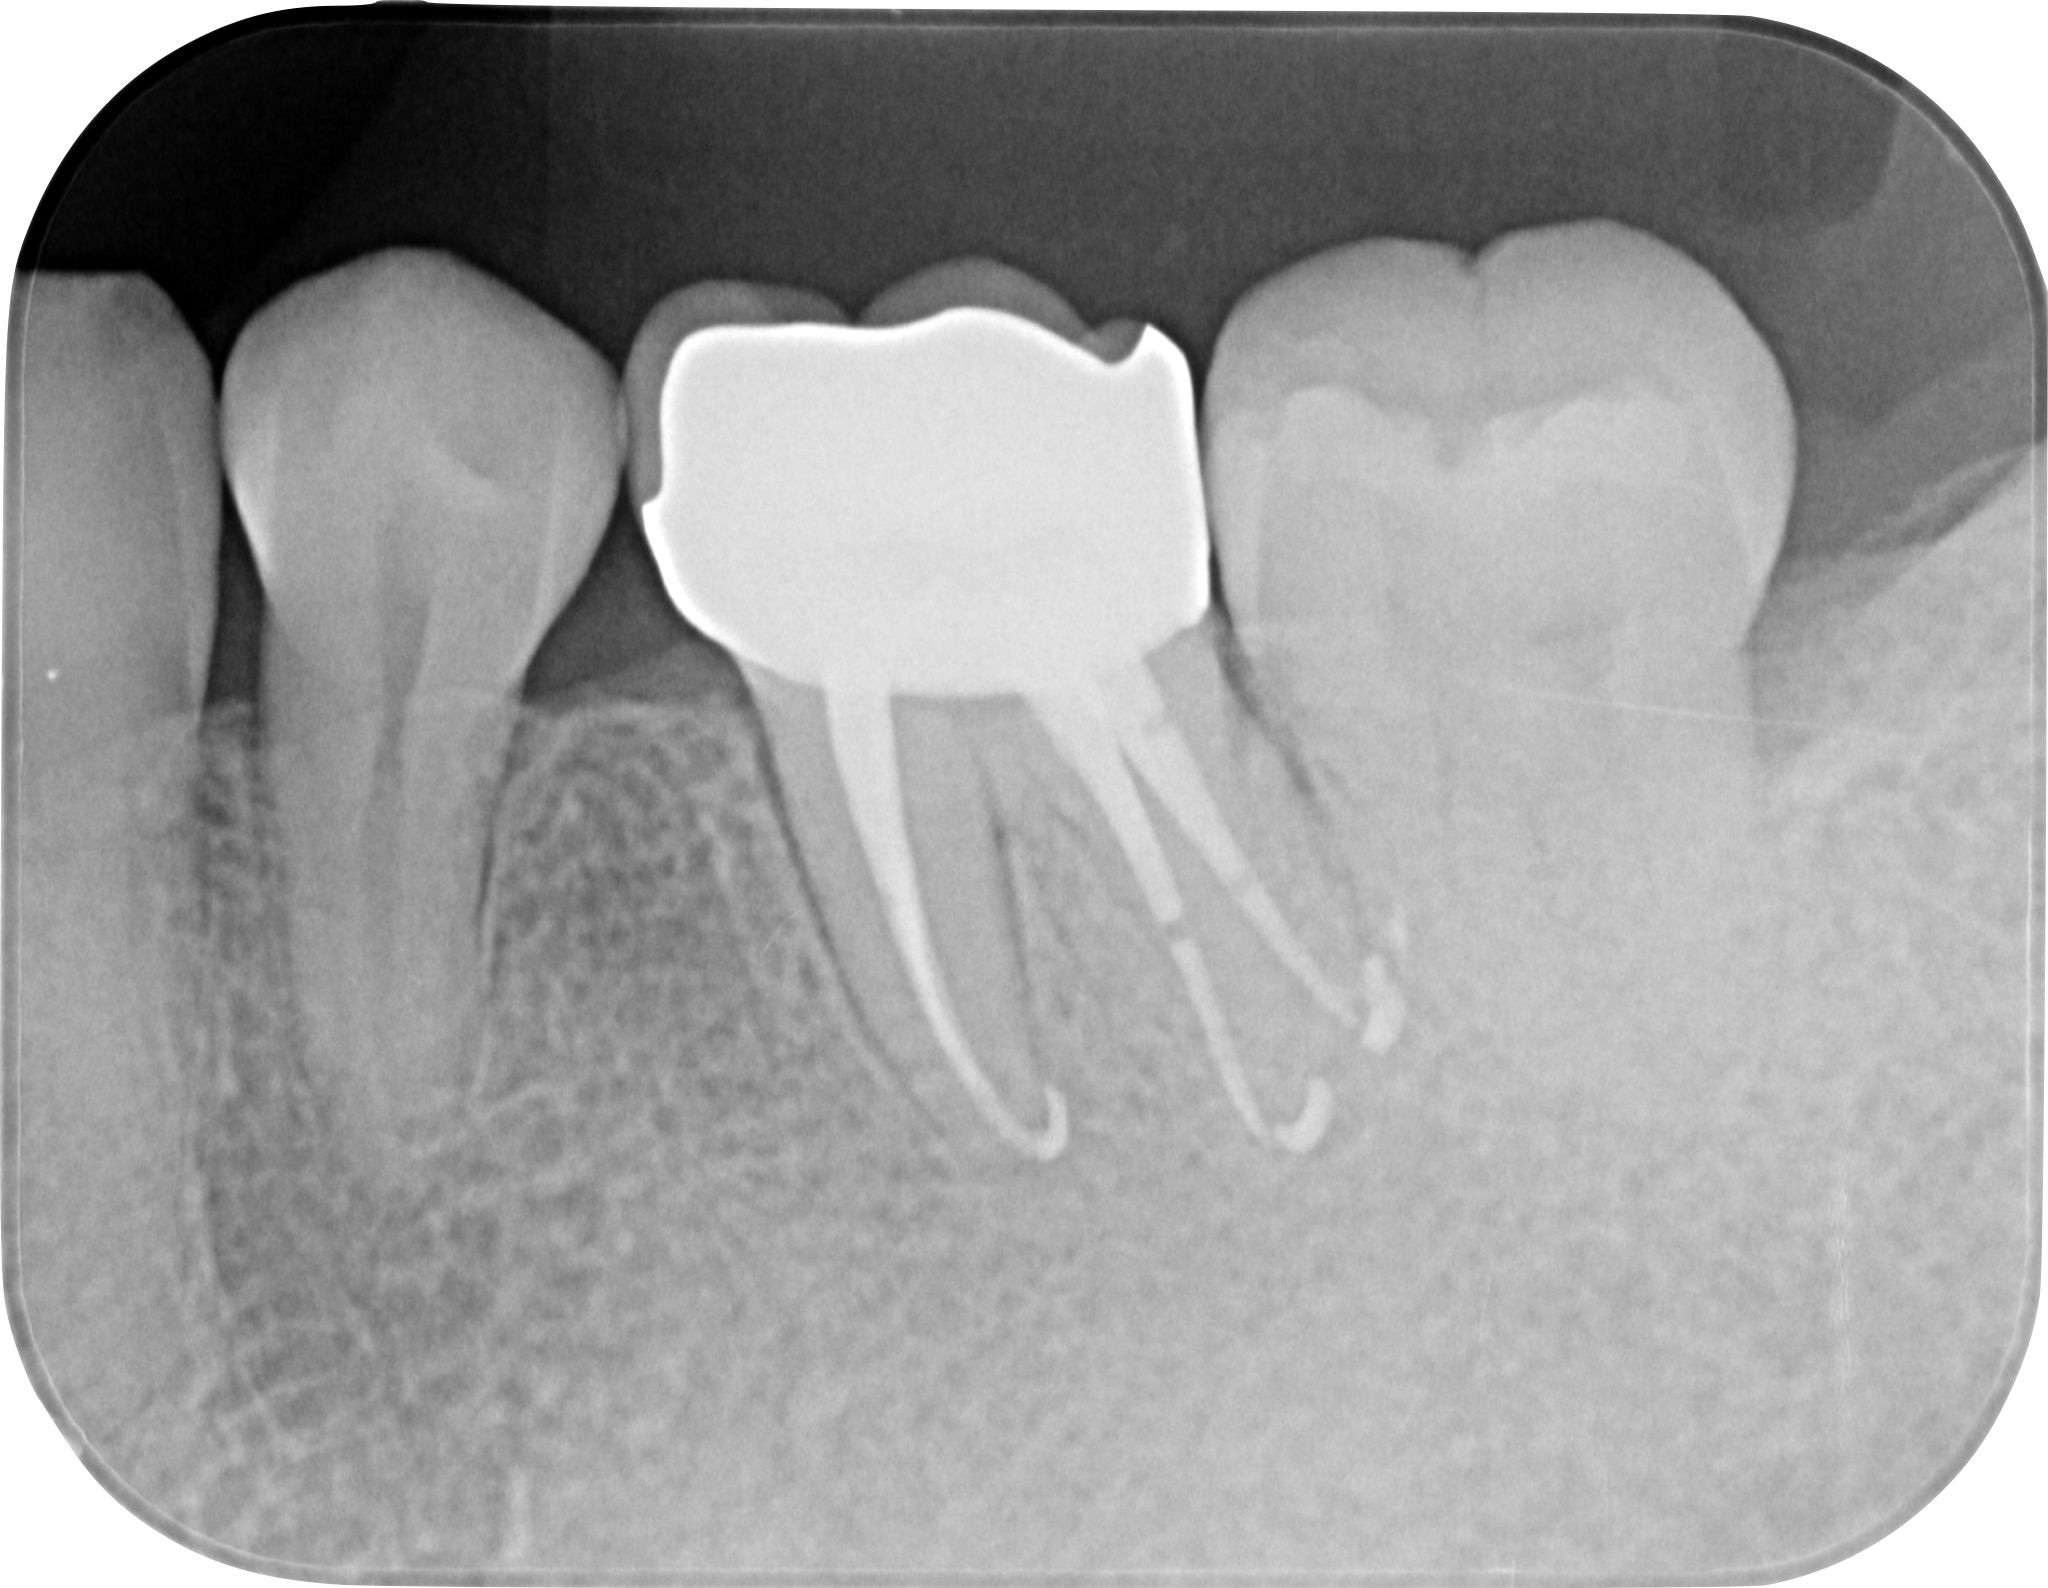

神経(歯髄)近くまたは神経自体にまで達したむし歯があるとき、外傷によって神経が露出したときに、MTAセメントという特殊なセメントを使用し、神経を残す治療です。

これまでであれば神経を除去するしかないケースでも、神経を残せる可能性があります。